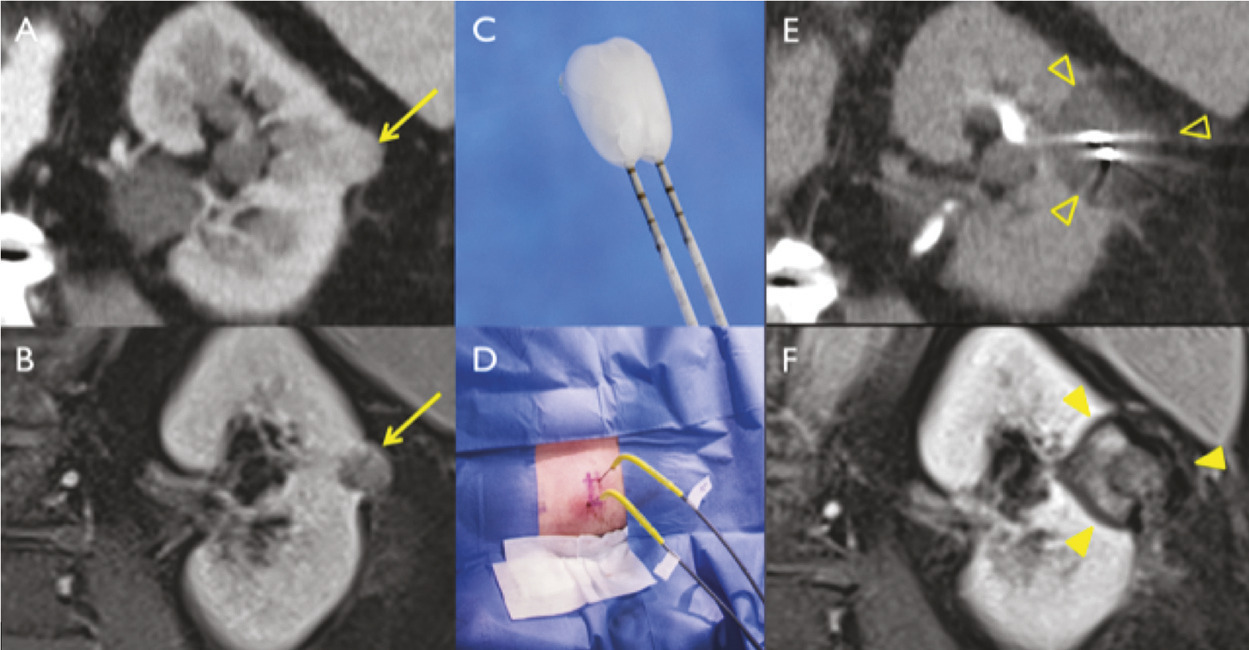

Pour chaque patient, un bilan d’hémostase est systématiquement réalisé avant la procédure. Pour les patients prenant des anticoagulants oraux, un relais par héparine de bas poids moléculaire est réalisé. Pour les antiagrégants plaquettaires, seul le clopidogrel doit être interrompu 5 jours avant. Le patient reçoit une prémédication par 1 g de paracétamol intraveineux 30 minutes avant la procédure. Il reste hospitalisé une nuit, mais une prise en charge ambulatoire est possible.La cryothérapie est réalisée sous anesthésie locale à l’aide d’un mélange de lidocaïne et de ropivacaïne. Contrairement à la radiofréquence ou aux micro-ondes où une seule électrode est insérée, la cryothérapie nécessite de mettre en place plusieurs aiguilles (cryoprobes) espacées au maximum de 15 mm afin de couvrir la totalité de la tumeur (fig. 1 ). Plus la tumeur est grosse, plus le nombre d’aiguilles à introduire est important. Il existe des abaques permettant de déterminer le nombre d’aiguilles optimal en fonction de la taille de la tumeur. Néanmoins, l’indication principale étant des tumeurs de stade T1a (< 4 cm de diamètre), le nombre moyen d’aiguilles est de 3, avec des extrêmes entre 2 et 5. Une injection de CO2 (carbodissection) ou de sérum physiologique (hydrodissection) est parfois nécessaire entre le rein et les organes adjacents afin de les éloigner de la zone d’ablation et les protéger.Les aiguilles sont mises en place sous tomodensitométrie et on vérifie leur bon positionnement. La dose délivrée lors d’une cryoablation rénale est inférieure aux niveaux de référence de dose recommandés pour une tomodensitométrie abdominale. Le traitement consiste en deux phases de cryoablation de 10 minutes entrecoupées d’une phase de réchauffement passif de 10 minutes également. L’effet cryogénique est obtenu par expansion d’un gaz (l’argon) dans une chambre de décompression de 2 à 4 cm de long située à l’extrémité de l’aiguille. Les températures minimales obtenues au contact de l’aiguille sont proches de -100 °C, en sachant qu’en moyenne la température de la tumeur se situe à -40 °C. La tomodensitométrie permet une excellente visualisation de la boule de glace, ce qui permet de monitorer l’ablation tout au long de la procédure. La boule de glace ainsi créée doit englober en totalité la tumeur et la dépasser de 5 mm afin d’avoir des marges de sécurité (fig. 2 ).6 En effet, le bord de la boule de glace est à l’isotherme 0 °C, qui n’est pas létal pour les tissus.Après traitement, le suivi des patients s’effectue par tomodensitométrie ou par imagerie par résonance magnétique (IRM), typiquement à 1 mois, 3 mois, 6 mois et 1 an, puis tous les ans. La zone d’ablation se rétracte progressivement et se fibrose, sans tumeur résiduelle visible (fig. 3 ). Pour les tumeurs de moins de 2 cm, le zone d’ablation disparaît parfois en totalité, laissant juste une encoche à la surface du rein (fig. 4 ). Les effets secondaires sont rares, la cryoablation étant mieux tolérée que les techniques d’ablation fondées sur le chauffage des lésions, en particulier pour les lésions proches de la voie excrétrice.7